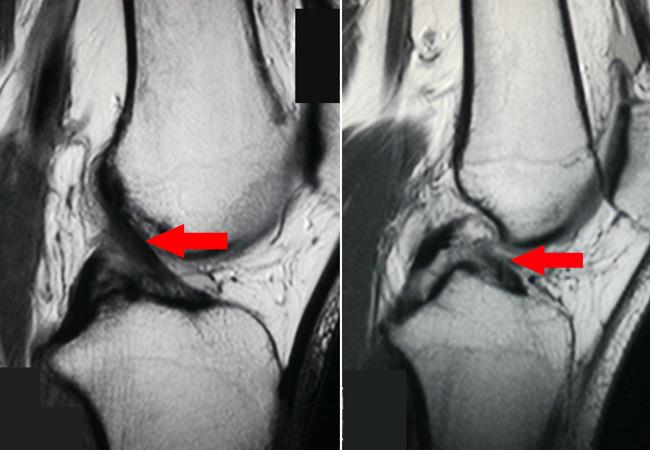

Η μαγνητική τομογραφία (MRI) είναι μια άλλη διαγνωστική τεχνική απεικόνισης που παράγει εικόνες εγκάρσιας τομής του σώματός σας. Σε αντίθεση με τις ακτίνες Χ και τις αξονικές τομογραφίες, οι μαγνητικές τομογραφίες λειτουργούν χωρίς ακτινοβολία. Το εργαλείο μαγνητικής τομογραφίας χρησιμοποιεί μαγνητικά πεδία και έναν εξελιγμένο υπολογιστή για να λαμβάνει εικόνες υψηλής ανάλυσης των οστών και των μαλακών ιστών σας.

Μια μαγνητική τομογραφία μπορεί να χρησιμοποιηθεί για να βοηθήσει στη διάγνωση ενός ευρέος φάσματος προβλημάτων, όπως ενδεικτικά:

- Ρήξη συνδέσμων γόνατος

- Ρήξεις μηνίσκου